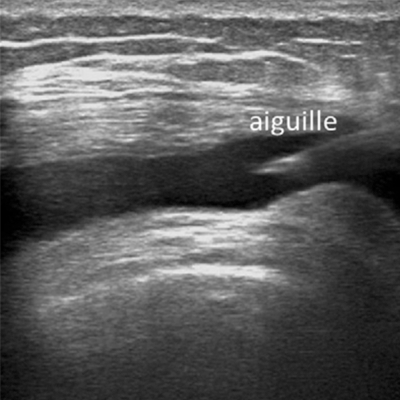

Infiltration sous guidage échographique

Ce mode d’infiltration est de plus en plus pratiqué pour les structures superficielles.

Il associe le caractère inoffensif de l’échographie, à la facilité d’exécution.

La mise en place de l’aiguille au contact de la zone à traiter et l’injection du médicament sont contrôlées en temps réel.

Aucun produit de contraste n’est nécessaire.